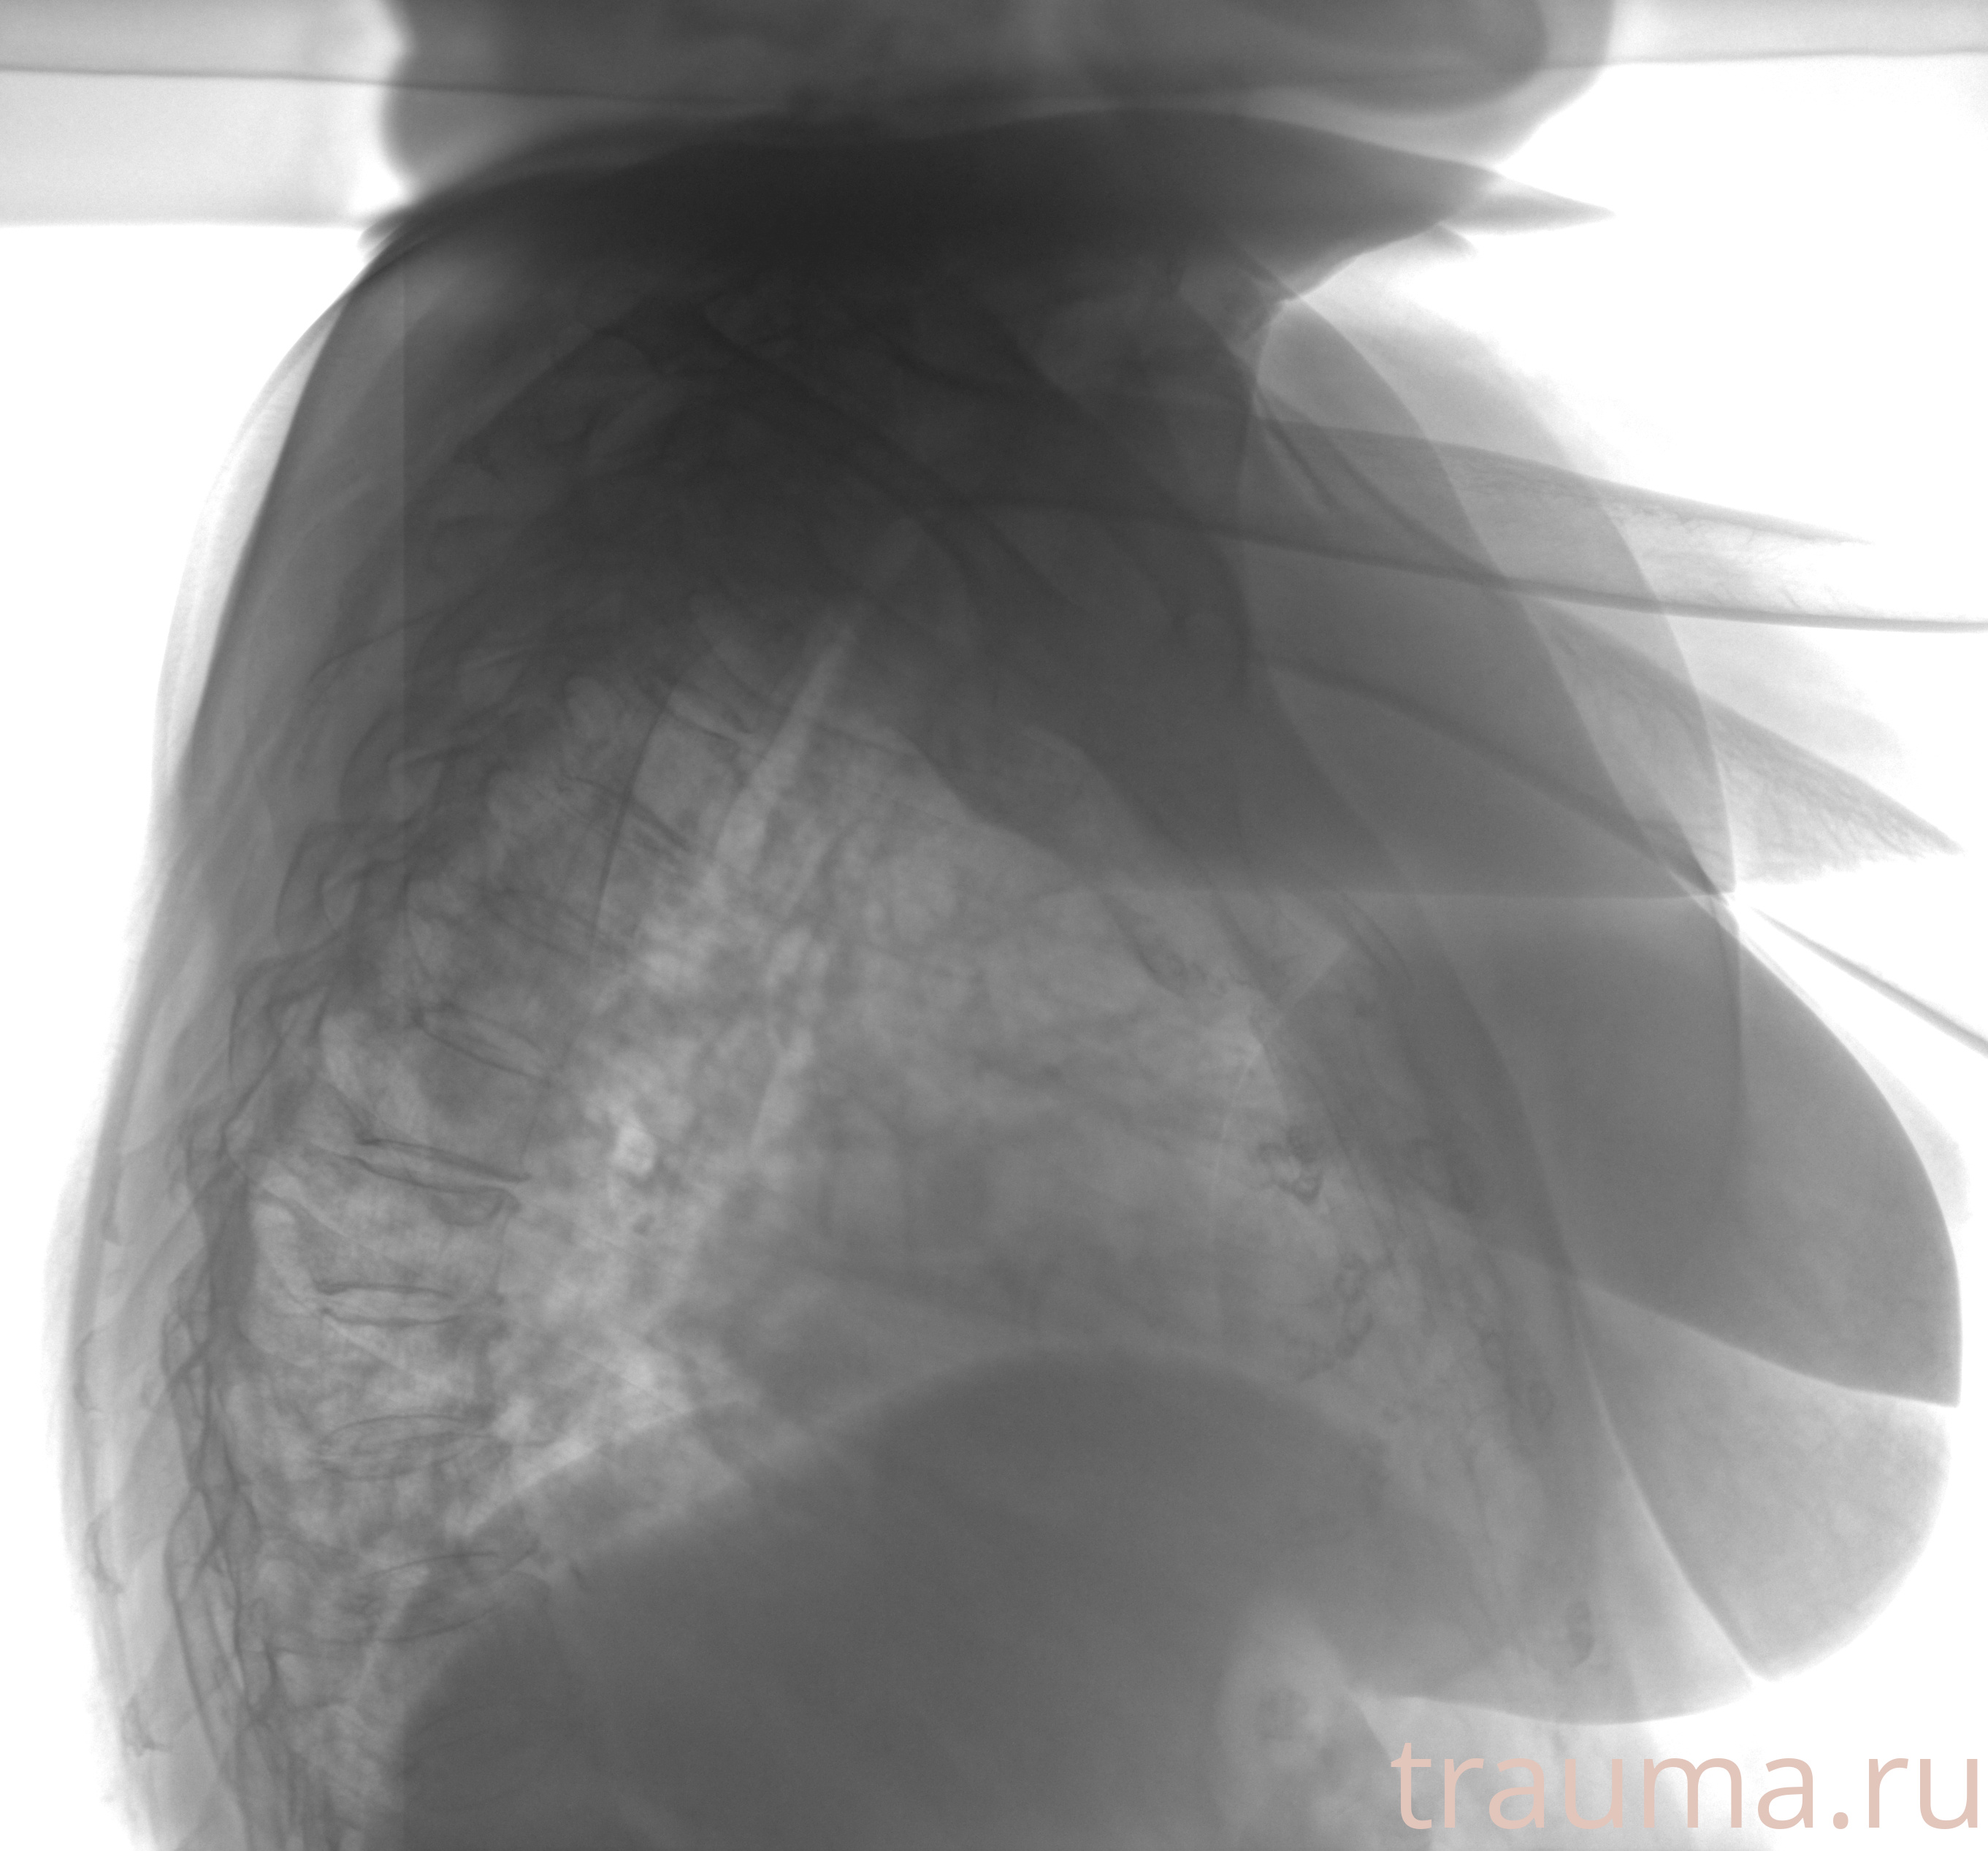

Рентген на дому: по вашему адресу приезжает врач-рентгенолог, травматолог-ортопед с мобильным рентгеновским аппаратом, проводит диагностику травмы или заболевания, делает необходимые рентгенограммы, дает рекомендации по дальнейшему лечению. Получить качественные снимки в домашних условиях возможно благодаря уникальной методике, разработанной МосРентген Центром для института  Склифосовского

при переломе шейки бедра и пневмонии от компании МосРентген Центр - партнера Института имени Склифосовского